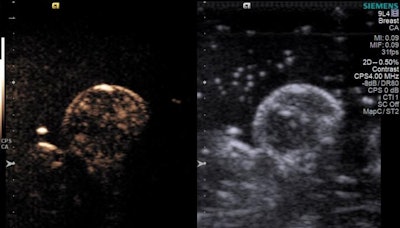

Microbubbles were originally developed to help improve ultrasound imaging. The idea of "popping" oxygen-filled microbubbles in tumors with ultrasound suggested a technique that could make radiation therapy more effective: Most solid tumors are deficient in oxygen, which also makes them resistant to radiation, according to the researchers.

Eisenbrey's group found that popping the microbubbles with ultrasound prior to radiation treatment tripled the cancer's sensitivity to radiation. It also almost doubled the survival time in mice, from 46 days with placebo, nitrogen-filled microbubbles to 76 days with oxygen-filled microbubbles.